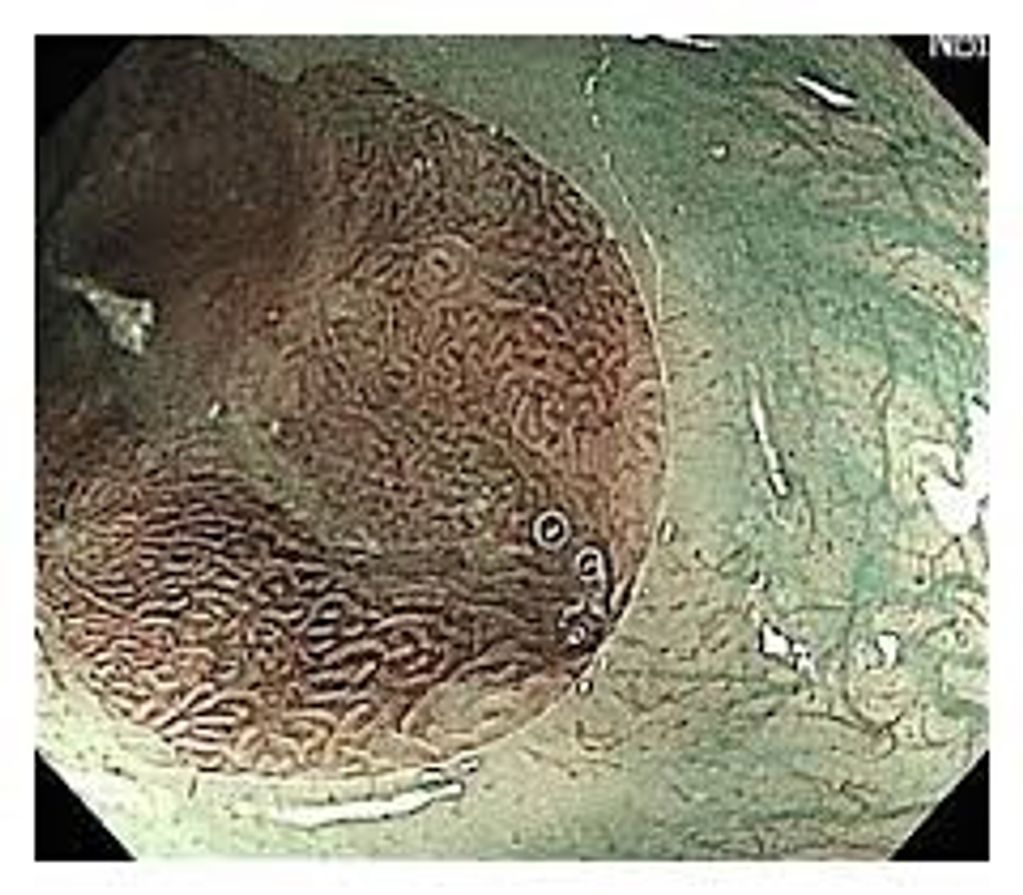

Endoscopic view of Barrett's esophagus

We use high definition video endoscopes with high magnification to assess the characteristics of the Barret's tissue. Note the visible gland structures

NBI or narrow band imaging is a wasy to better see Barret's changes by changing the wavelength of the endoscope light. Dr Gorcey uses NBI as well as white light during all his endoscopies and colonoscopies (better polyp detection) for a more sensitive exam.